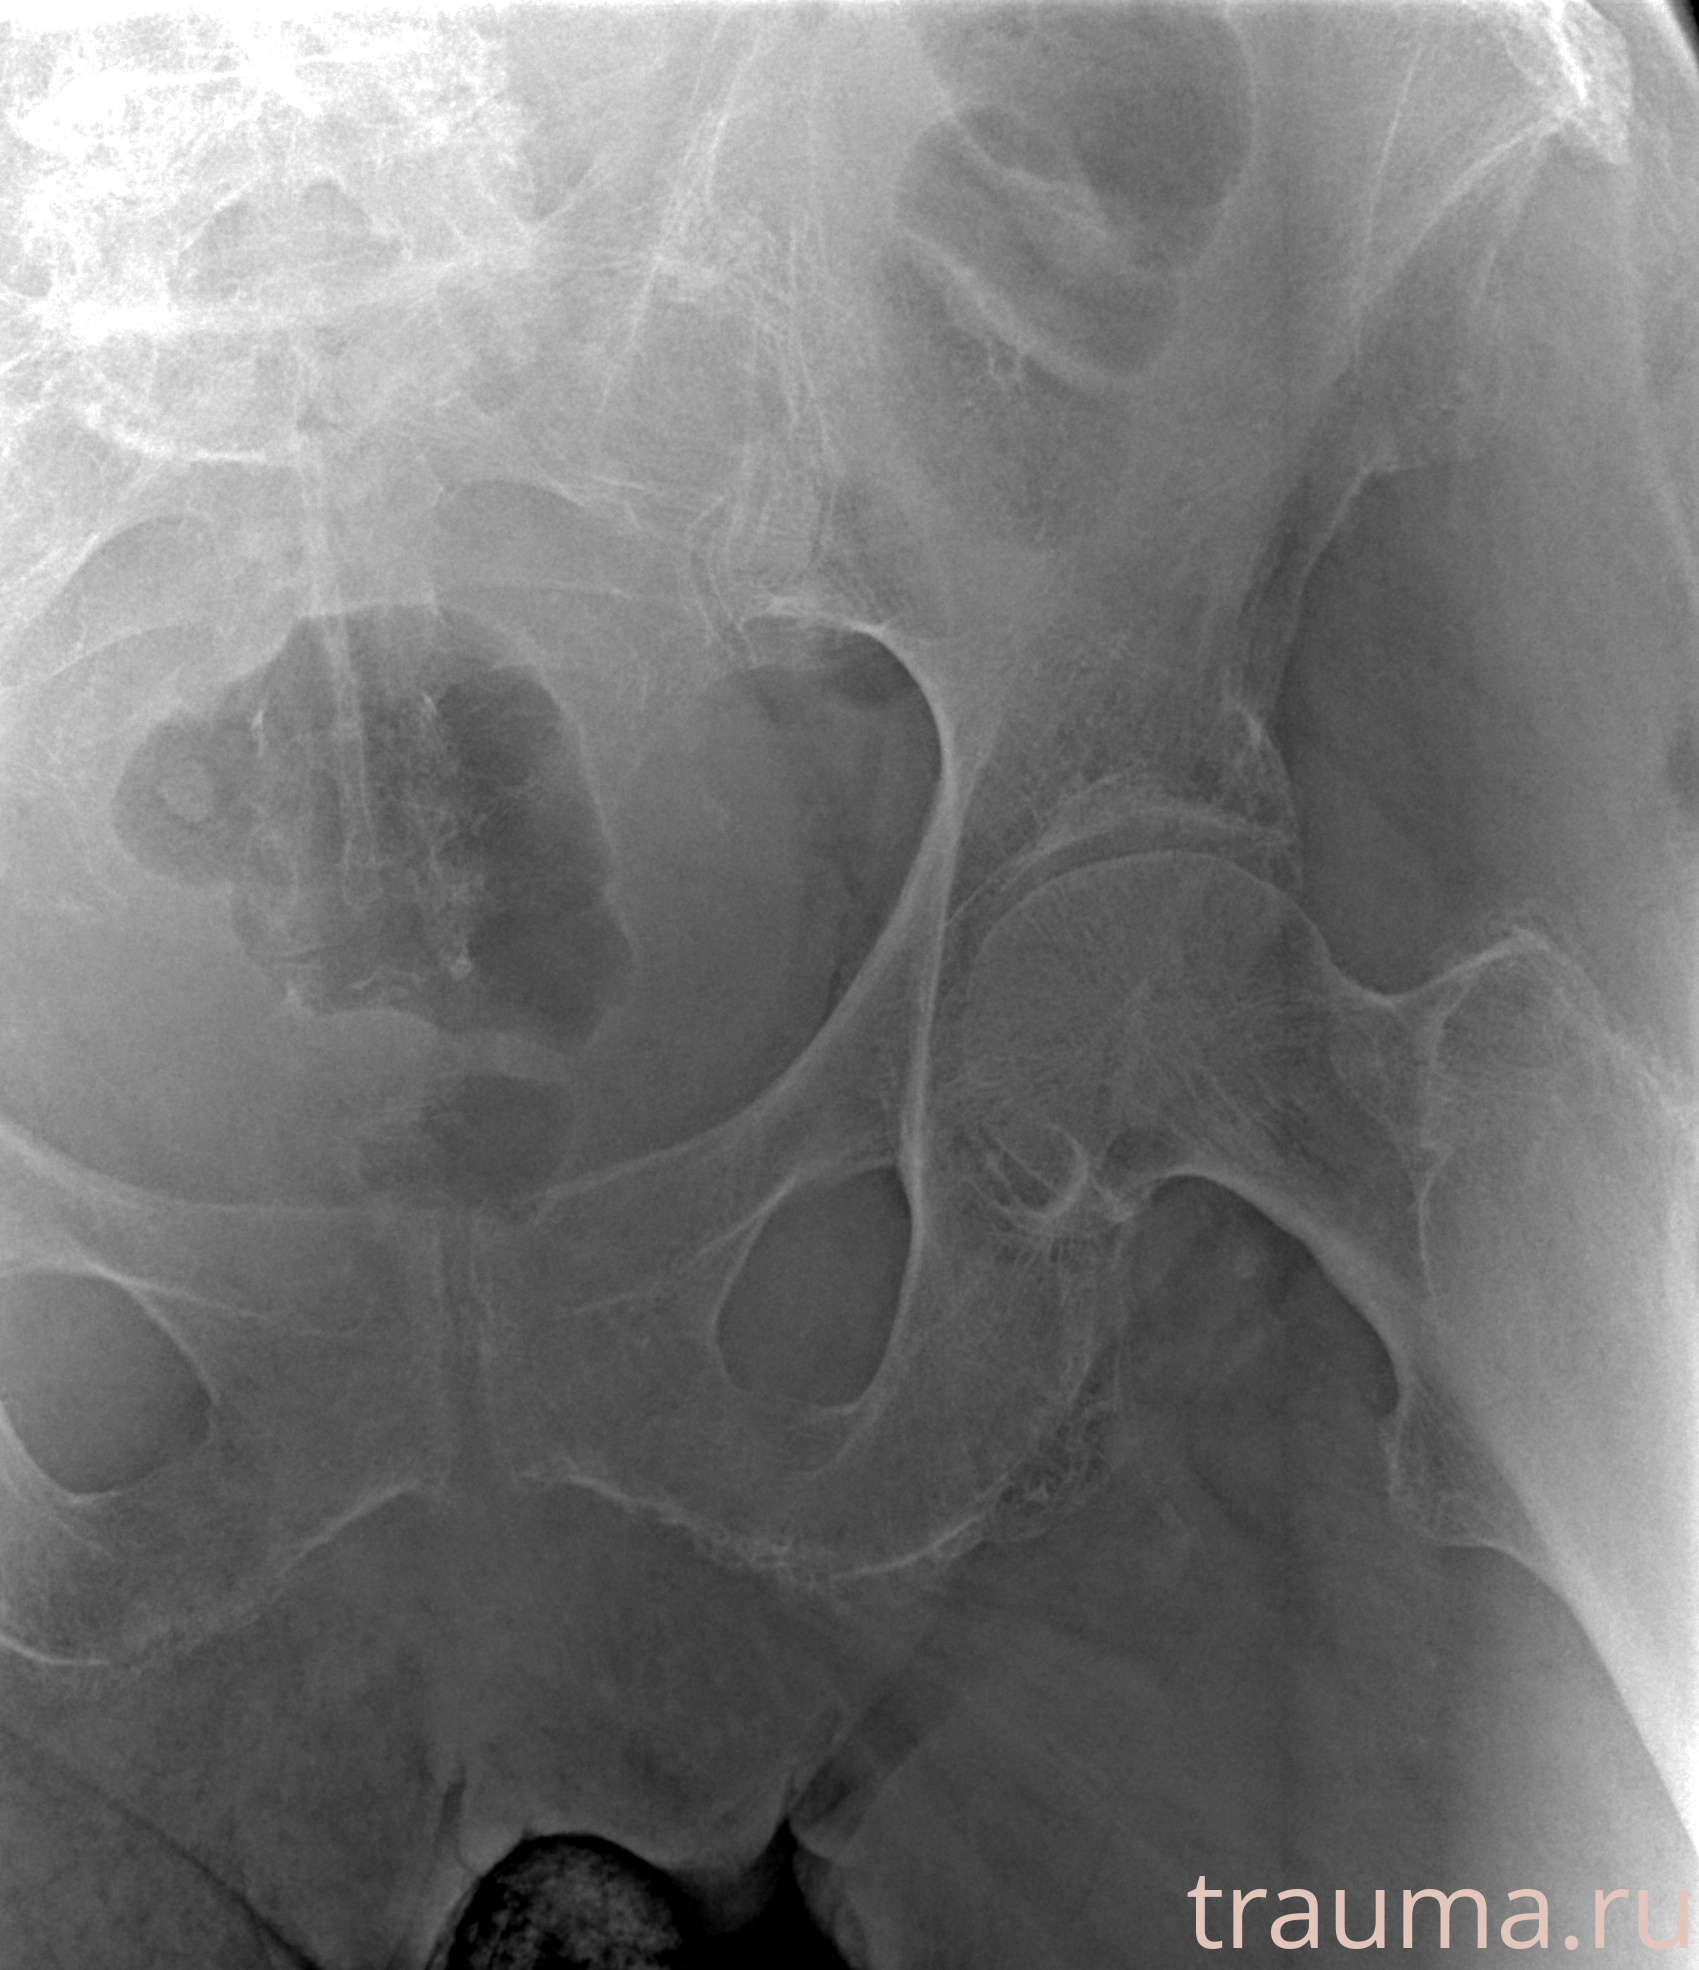

Рентгенограммы

Рентген на дому: по вашему адресу приезжает врач-рентгенолог, травматолог-ортопед с мобильным рентгеновским аппаратом, проводит диагностику травмы или заболевания, делает необходимые рентгенограммы, дает рекомендации по дальнейшему лечению. Получить качественные снимки в домашних условиях возможно благодаря уникальной методике, разработанной МосРентген Центром для института  Склифосовского